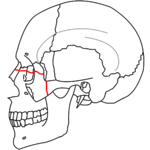

At the beginning of the 20th century, René Le Fort mapped typical locations for facial fractures; these are now known as Le Fort I, II, and III fractures (right).[6] Le Fort I fractures, also called Guérin or horizontal maxillary fractures,[13] involve the maxilla, separating it from the palate.[14] Le Fort II fractures, also called pyramidal fractures of the maxilla,[15] cross the nasal bones and the orbital rim.[14] Le Fort III fractures, also called craniofacial disjunction and transverse facial fractures,[16] cross the front of the maxilla and involve the lacrimal bone, the lamina papyracea, and the orbital floor, and often involve the ethmoid bone.[14] are the most serious.[17] Le Fort fractures, which account for 10–20% of facial fractures, are often associated with other serious injuries.[14] Le Fort made his classifications based on work with cadaver skulls, and the classification system has been criticized as imprecise and simplistic since most midface fractures involve a combination of Le Fort fractures.[14] Although most facial fractures do not follow the patterns described by Le Fort precisely, the system is still used to categorize injuries.[5]

Incising wounds of the face may involve the parotid duct. This is more likely if the wound crosses a line drawn between the tragus of the ear to the upper lip. The approximate location of the course of the duct is the middle third of this line.[24]